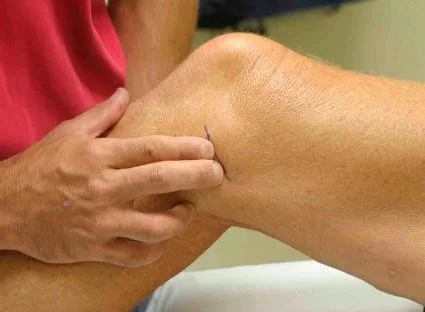

Knee Aspiration

https://www.youtube.com/watch?v=sRVAzsZEBVY&pp=ygUUS25lZSBhc3BpcmF0aW9uIG9zY2U%3D https://www.youtube.com/watch?v=ikXvLLlpoas&pp=ygUUS25lZSBhc3BpcmF0aW9uIG9zY2U%3D

| Item | Procedure |

| Preparation / position Ask student | Patient in supine position Knee straight - slightly flexed (15-20°) on small support |

| Aspiration |

| Post procedure instructions |